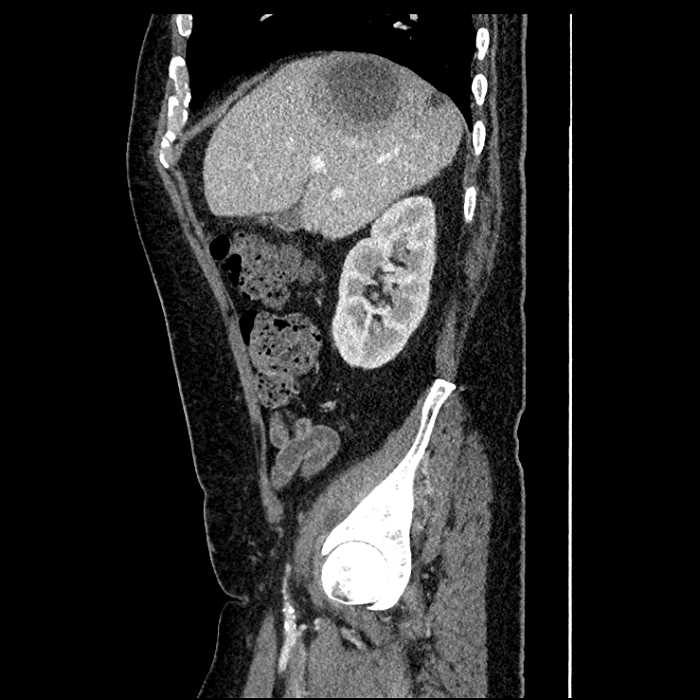

Age: 63

Sex: Male

Indication: Abdominal pain

• Large fluid density structure in hepatic segments 7 and 8 measuring 10 x 7 x 7 cm with internal septation and circumferential ill-defined low density compatible with edema

• Peripherally enhancing subcapsular collections along the anterior margin of the left hepatic lobe measuring 3 x 1 cm and 2 x 1 cm

• Clearly marginated fluid density structure in segment 7 and several other scattered tiny hypodensities, which likely represent cysts

• Hepatic abscess

Acute sigmoid diverticulitis complicated by a small contained perforation and a large abscess in the right hepatic lobe. Additional small subcapsular abscesses along the anterior margin of the left hepatic lobe.

• The classic CT imaging appearance is a double target sign with internal low density surrounded by an internal enhancing rim (capsule) and a low density external rim (edema)

Hepatic abscess showing the double target sign with low density internally surrounded by a thin inner enhancing rim (red arrow) and ill-defined outer low density rim (yellow arrow). Blue arrow indicates an internal septation. Red arrows: additional smaller subcapsular abscesses. Red arrow: focal contained perforation associated with diverticulitis.